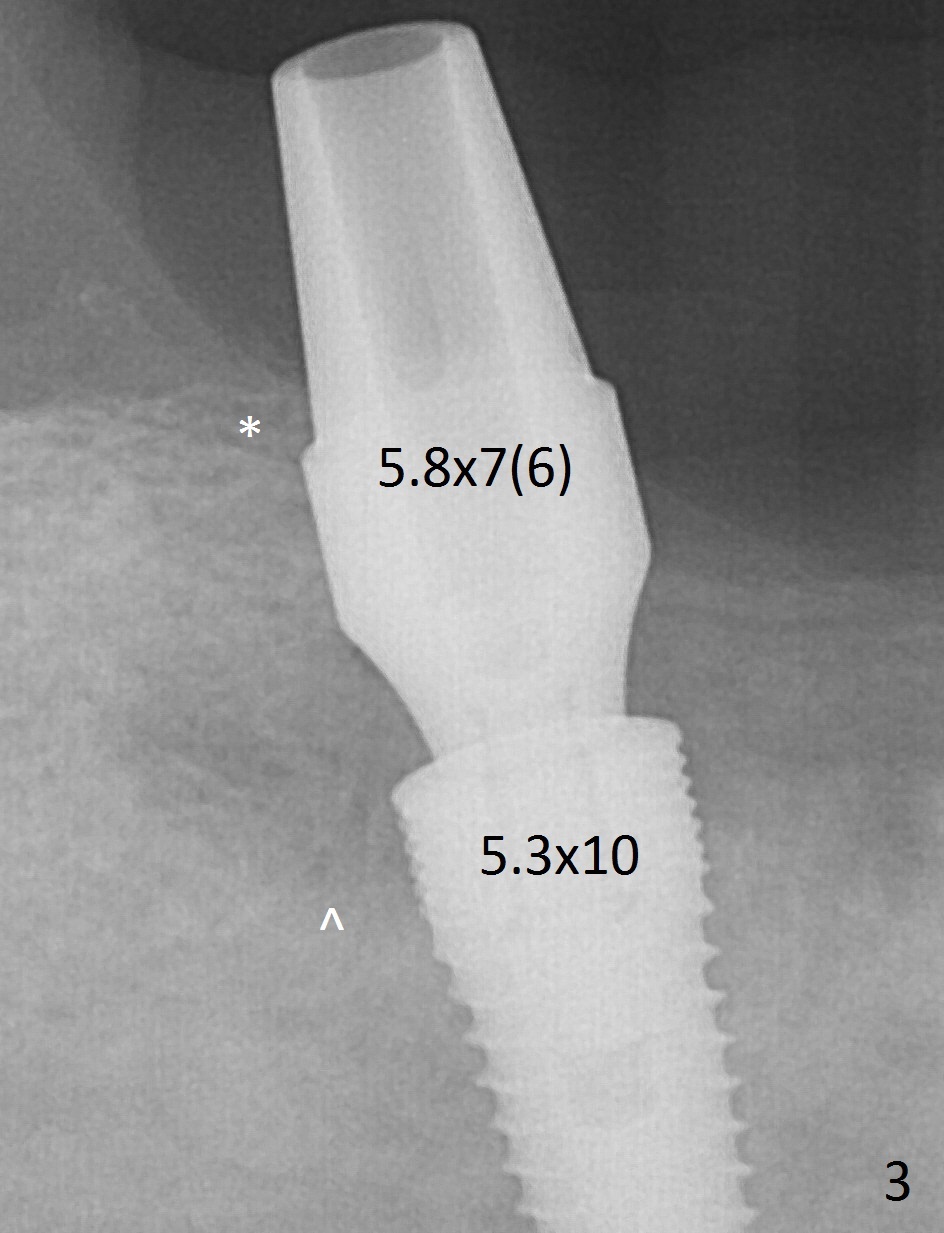

At #31, the implant has to be placed low because of low buccal bone (Fig.8 B (vs. much higher lingual (L) one) in spite of 2 mm implant being coronal to the distal bone (Fig.3 ^). The margin of the abutment with 6 mm cuff appears apical to the distal crest (Fig.3 *). Bone graft is placed around the exposed implant threads (Fig.6 *) after placement of Osteogen plug between the implants (P). After placing PRF membrane (Fig.7 M) and plug (P) over the bone graft, Cytoplast (Fig.6,8 C: non-resorbable membrane) is used to assist wound closure. Finally periodontal dressing is applied for further wound protection (Fig.9).